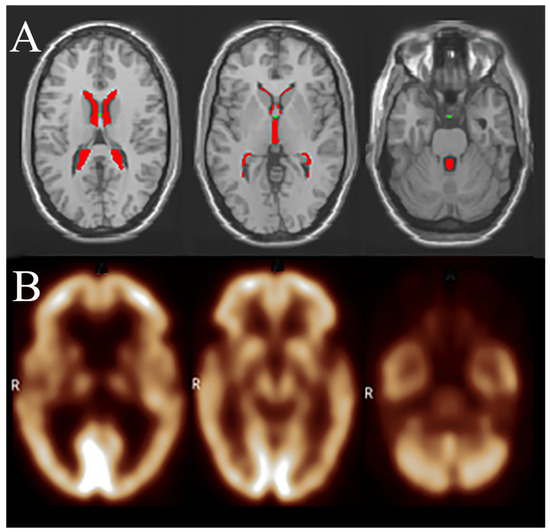

Figure 1.

An exemplificative representation of the methodological approach used in this study for defining regions of interest (ROIs) using the WFU PickAtlas tool implemented in SPM12. Upper row (A): anatomical MRI images displaying ventricular ROIs (highlighted in red). These ventricular ROIs, derived through the WFU PickAtlas, were subsequently applied to PET scans of the patients included in the analysis. Lower row (B): corresponding 18F-FDG PET images, onto which the ventricular ROIs were mapped to measure 18F-FDG in CSF. The 18F-FDG values were normalized to pons activity to correct for individual metabolic variability, thus enabling the assessment of cerebrospinal fluid glucose dynamics in relation to Alzheimer’s disease pathophysiology. The ventricles in PET images may appear larger than those in MRI due to the lower 18F-FDG uptake in surrounding white matter. This image is intended purely to clarify the methodological approach and does not represent the exact methodological procedure used in this study (see text for detailed information). R: right side.

ROIs for ventricles specifically included lateral ventricles as predefined by the WFU PickAtlas. Cortical ROIs were defined as a composite cortical mask encompassing frontal, parietal, temporal, and occipital lobes using the anatomical label atlas in WFU PickAtlas [23]. A dataset of normalized 18F-FDG values relevant to the cluster under study was exported. To determine whether the normalized 18F-FDG values for the studied cluster were Gaussian distributed, the D’Agostino K-squared normality test was applied (with the null hypothesis being normal distribution).